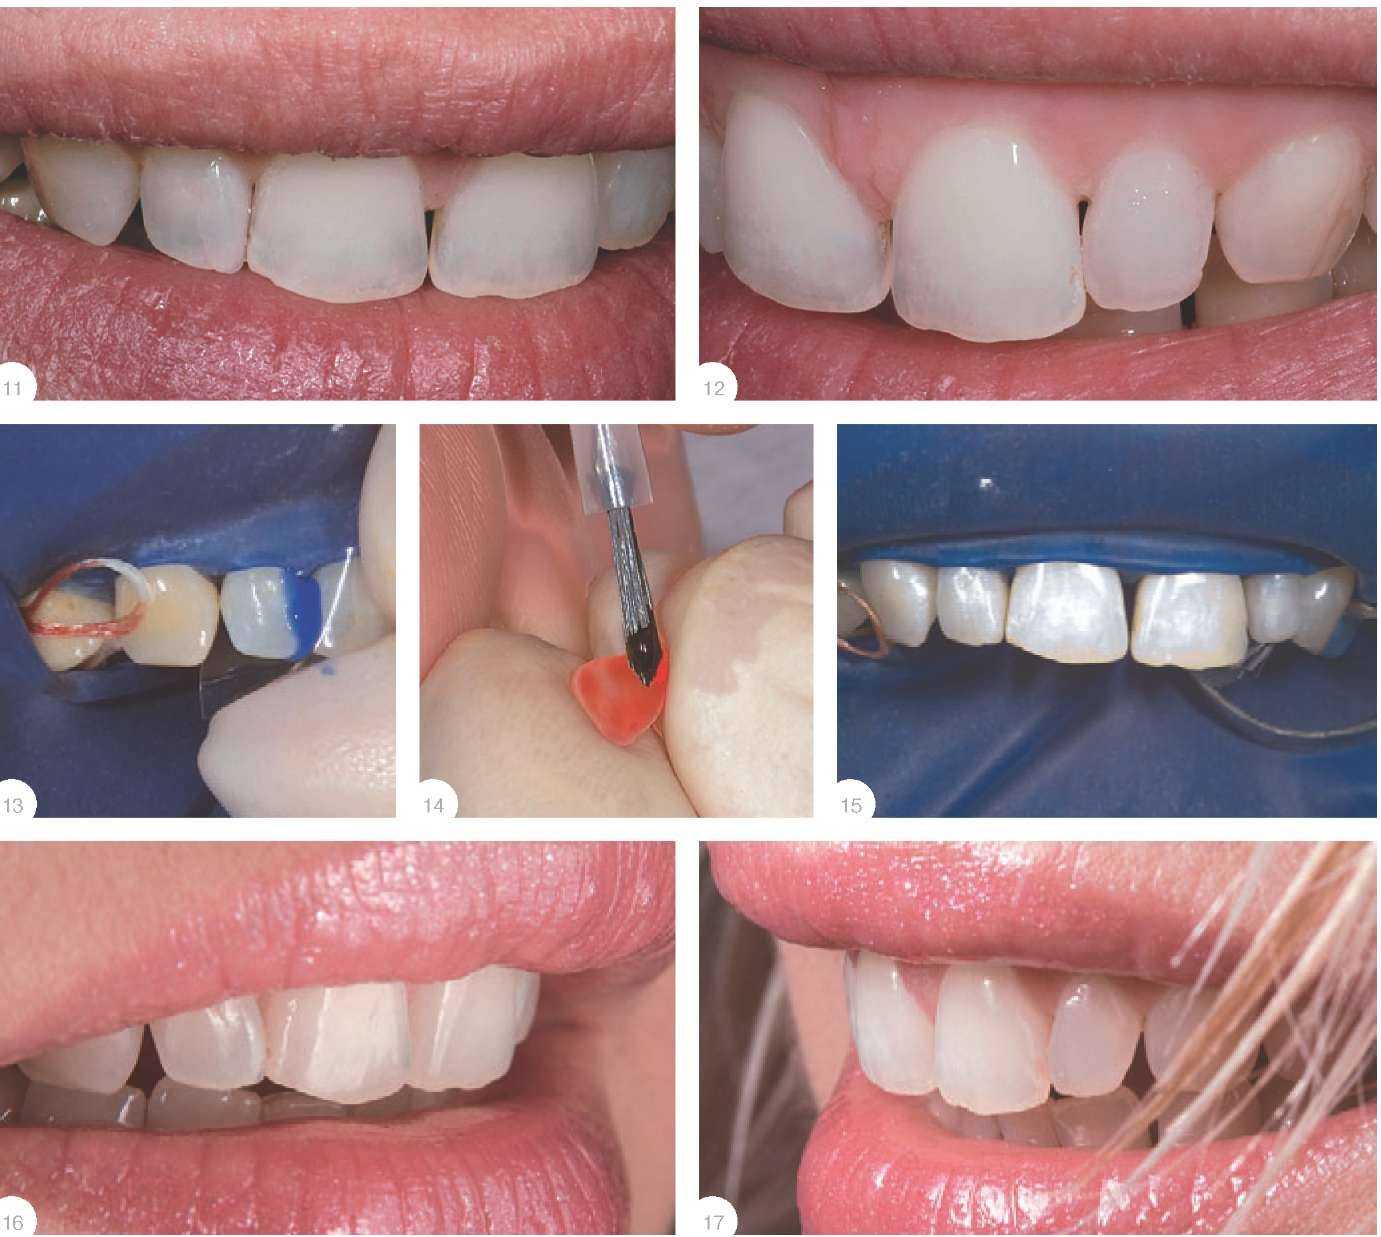

Инструкции по установке виниров, шаг за шагом, с иллюстрациями и фотографиями процесса и окончательных результатов.

🔎 Процесс изготовления и установки виниров. Как устанавливают виниры. Легкое Дыхание. 12+

ВИНИРЫ! Процесс установки. Стоматология Мастер Мед

Виниры. Все этапы установки и изготовления - Зубы до и после установки виниров - Дентал ТВ 12+